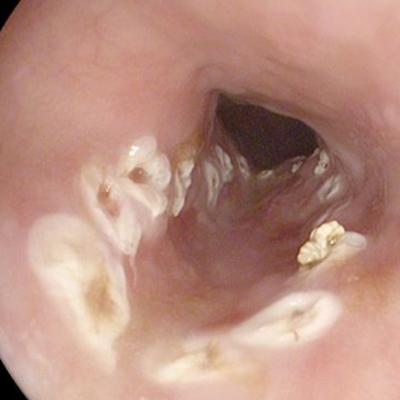

直腸癌圖片